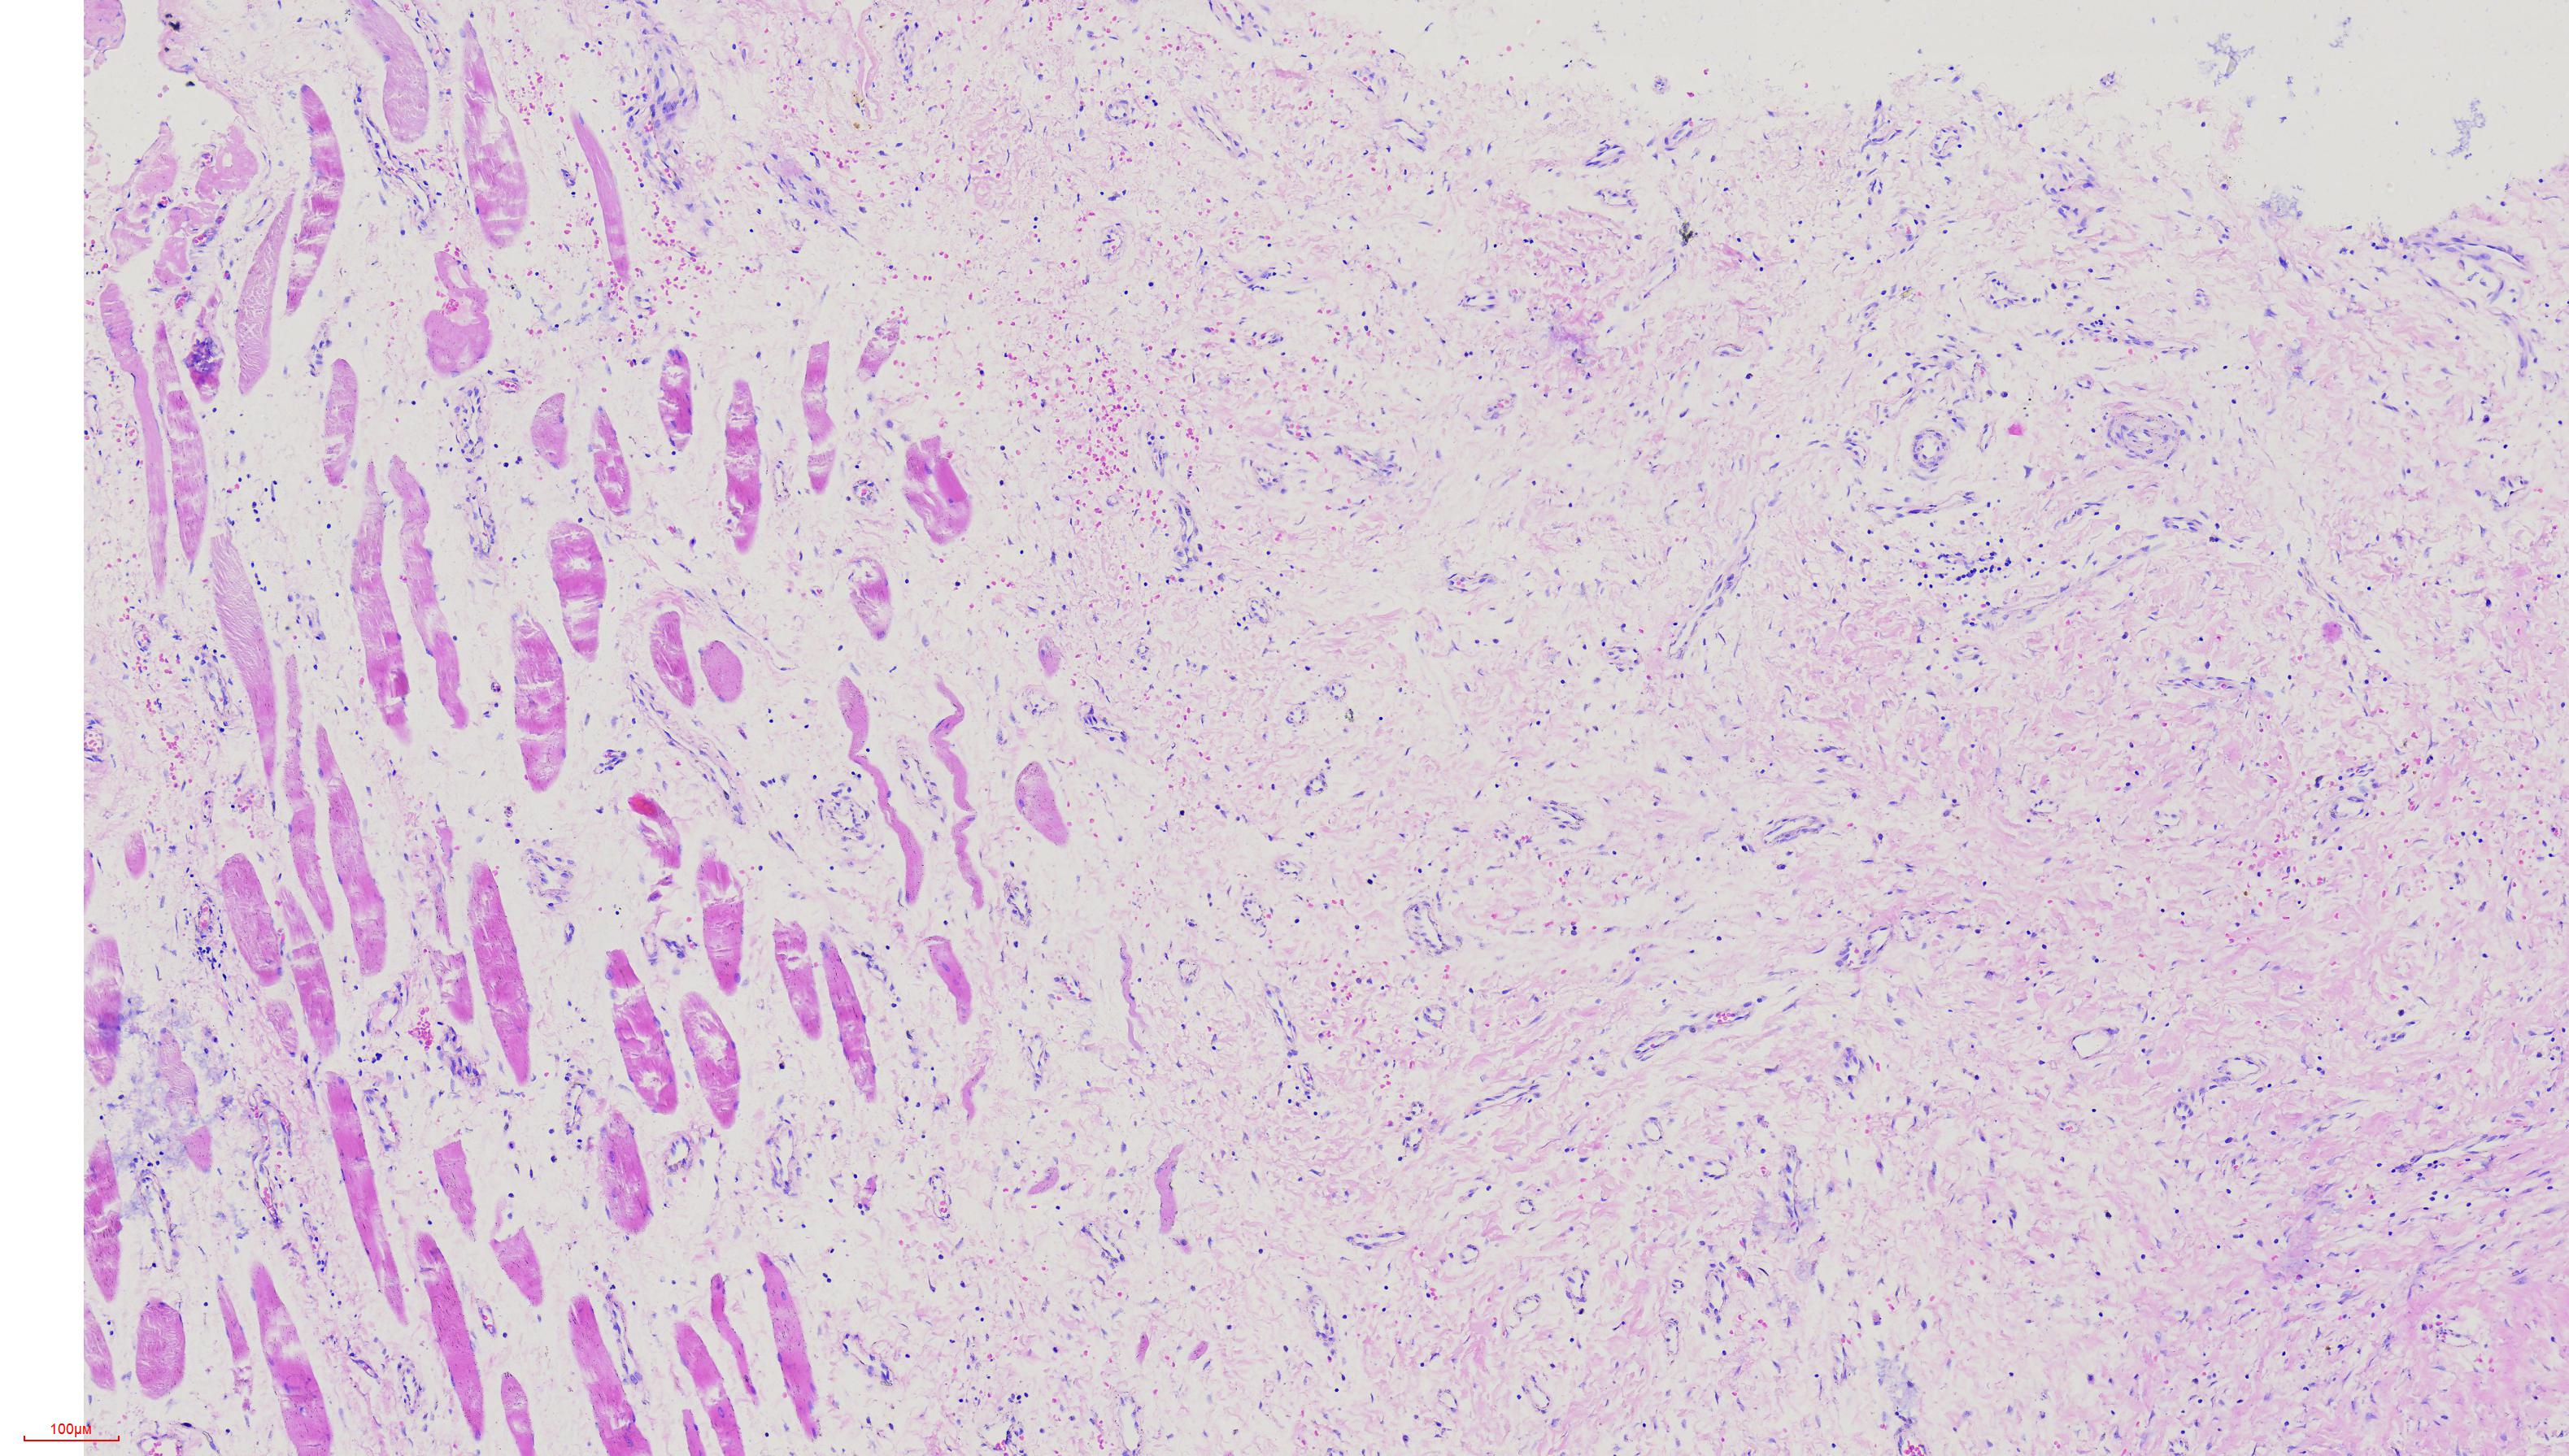

肘关节肿物

性别

女

年龄

46岁

结节状组一块

图1

横纹肌、血管、纤维组织,描述诊断